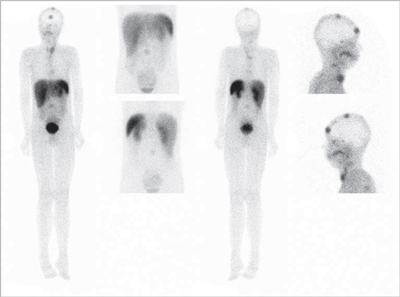

Es un tumor endocrino del páncreas muy poco frecuente, se calcula su incidencia anual en 0,5-3 casos por millón de habitantes. Casi siempre está ubicado en el páncreas (1/3 en la cabeza, 1/3 en el cuerpo y 1/3 en la cola) aunque puede tener localizaciones ectópicas: duodeno, divertículo de Meckel, vía biliar, ovario y omento. Generalmente son pequeños: 40% son menores de 1 cm y 50% entre 1 y 5 cm y generalmente solitarios. Menos del 10% son múltiples, en cuyo caso debe descartarse síndrome de NEM tipo 1. Menos del 10% son malignos y 5% se presentan con metástasis, generalmente en el hígado o adenopatías regionales27 (Figura 10). Los insulinomas benignos y malignos suelen expresar receptores de somatostatina, el más frecuente es el subtipo 4 (80-90% de los casos), de moderada (10-50%) a gran intensidad (> 50% de las células tumorales) en los estudios inmunohistoquímicos. Los subtipos 1, 2 y 3 se expresan esporádicamente (40-50% de los casos) en los insulinomas benignos y malignos,generalmente en menos del 10% de las células neoplásicas. Los insulinomas benignos no expresan sstr 5 mientras que algunos malignos sí lo hacen28. Estos hallazgos están en línea con la experiencia clínica: aproximadamente el 50% de los insulinomas son positivos en la cintigrafía con pentatreotide y el tratamiento con radiopéptidos análogos de somatostatina (Lu177-DOTATATE o Y90-DOTATOC) es paliativo y sirve para ayudar al control de la hipoglicemia de estos enfermos29 (Figura 11).

Fusión SPECT/RM. Imágenes transaxiales de RM y SPECT con In111- pentatreotide.

Paciente con insulinoma metastásico. Se demuestra intensa sobreexpresión de receptores de somatostatina en metástasis hepáticas múltiples.